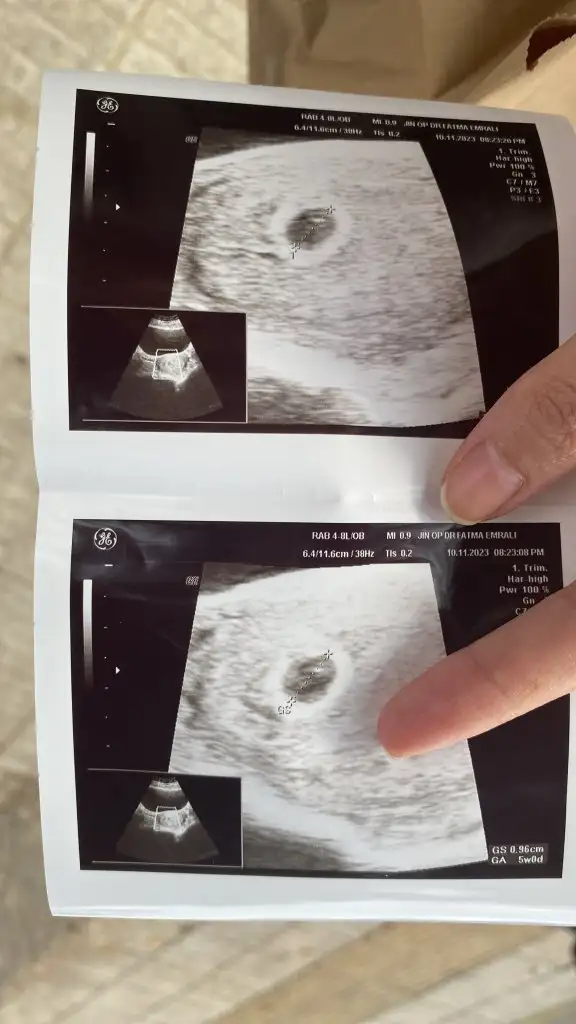

Dün kan verdim 4043 çıktı bugün doktora gittim kesem gözüktü, cuma tekrar idrara sıkışıp gel dedi sizce normal mi

Kalbini ferah tut rabbine güven benim kesem 2.10 cm ama boş gebelik tanısı konuldu şuan nasip kısmet kalbini ferah tut ki güzel olsun inşallah

En son kontrolüm 24 kasımda tekrar gideceğim